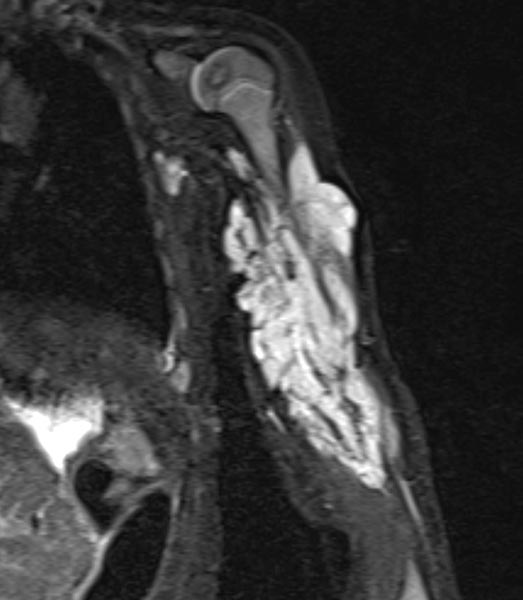

Zur weiteren Sicherung der Differentialdiagnose wird bei dem Kind auch eine MRT durchgeführt. Hier abgebildet eine koronare, T2-gewichtete, fettunterdrückte STIR-Sequenz. Der Tumor ist hier stark hyperintens (weiß im Bild) und scharf zum umgebenden Gewebe abgegrenzt. Er durchdringt alle Gewebeebenen und enthält zentral als Zeichen einer starken arteriellen Perfusion signalfreie Areale, sogenannte Flow-voids.

Zur weiteren Klärung der Differentialdiagnose wurde nochmals eine MRT durchgeführt, hier wieder abgebildet eine koronare, T2-gewichtete, fettunterdrückte STIR-Sequenz. Der Tumor ist jetzt etwas weniger stark hyperintens (weniger weiß), dies spricht für einen etwas höheren Fettanteil in dieser fettunterdrückten Sequenz. Auch die Perfusion hat etwas abgenommen, es finden sich im Vergleich weniger Flow-voids.